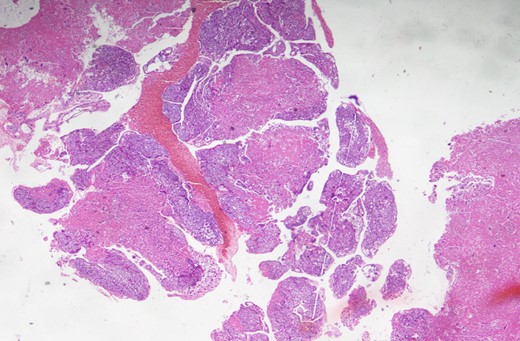

A 25-year-old lady was admitted in the pulmonology ward with the diagnosis of pneumonia. The patient had presented with a history of progressive shortness of breath, chest pain and persistent cough with occasional haemoptysis. She had a history of being treated with antibiotics and anti-TB drugs in outpatient basis. She had had spontaneous abortion 8 months back. Since her symptoms were persistent and her general condition was deteriorating, she was admitted to the ward. On examination, she had crepitations in bilateral chest and an oxygen saturation of only 80%. Chest X-ray showed bilateral infiltrations. CECT chest was done, which revealed pulmonary embolus occluding the main pulmonary artery, and right and left pulmonary arteries (Fig. 1). Venous Doppler did not reveal thrombosis of the lower limbs or IVC. Pulmonary thromboembolectomy was done and embolus (Fig. 2) was sent for histopathological examination. The examination revealed it to be metastatic choriocarcinoma (Fig. 3). Serum beta-human chorionic gonadotrophin (HCG) level was found to be significantly high. CECT pelvis and head were negative for pelvic and CNS metastases. She was managed further with chemotherapy (EMACO regimen) with excellent response to the treatment.